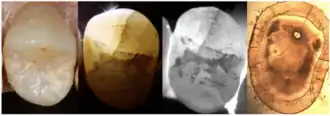

3. Dye Test

Dye application, using agents such as methylene blue can enhance the visibility of cracks (Yu et al., 2022). The dye test is limited in that it can only locate cracks but not assess their progression. Additionally, bacterial infiltration of cracks can cause discoloration that is difficult to remove, affecting aesthetics and treatment outcomes.

4. Transillumination

Transillumination involves using fiber-optic light to illuminate the tooth surface, with light diffraction at the crack helping to locate it (Chanchala HP et al., 2022).

Microscopic Detection

5. Microscope detection